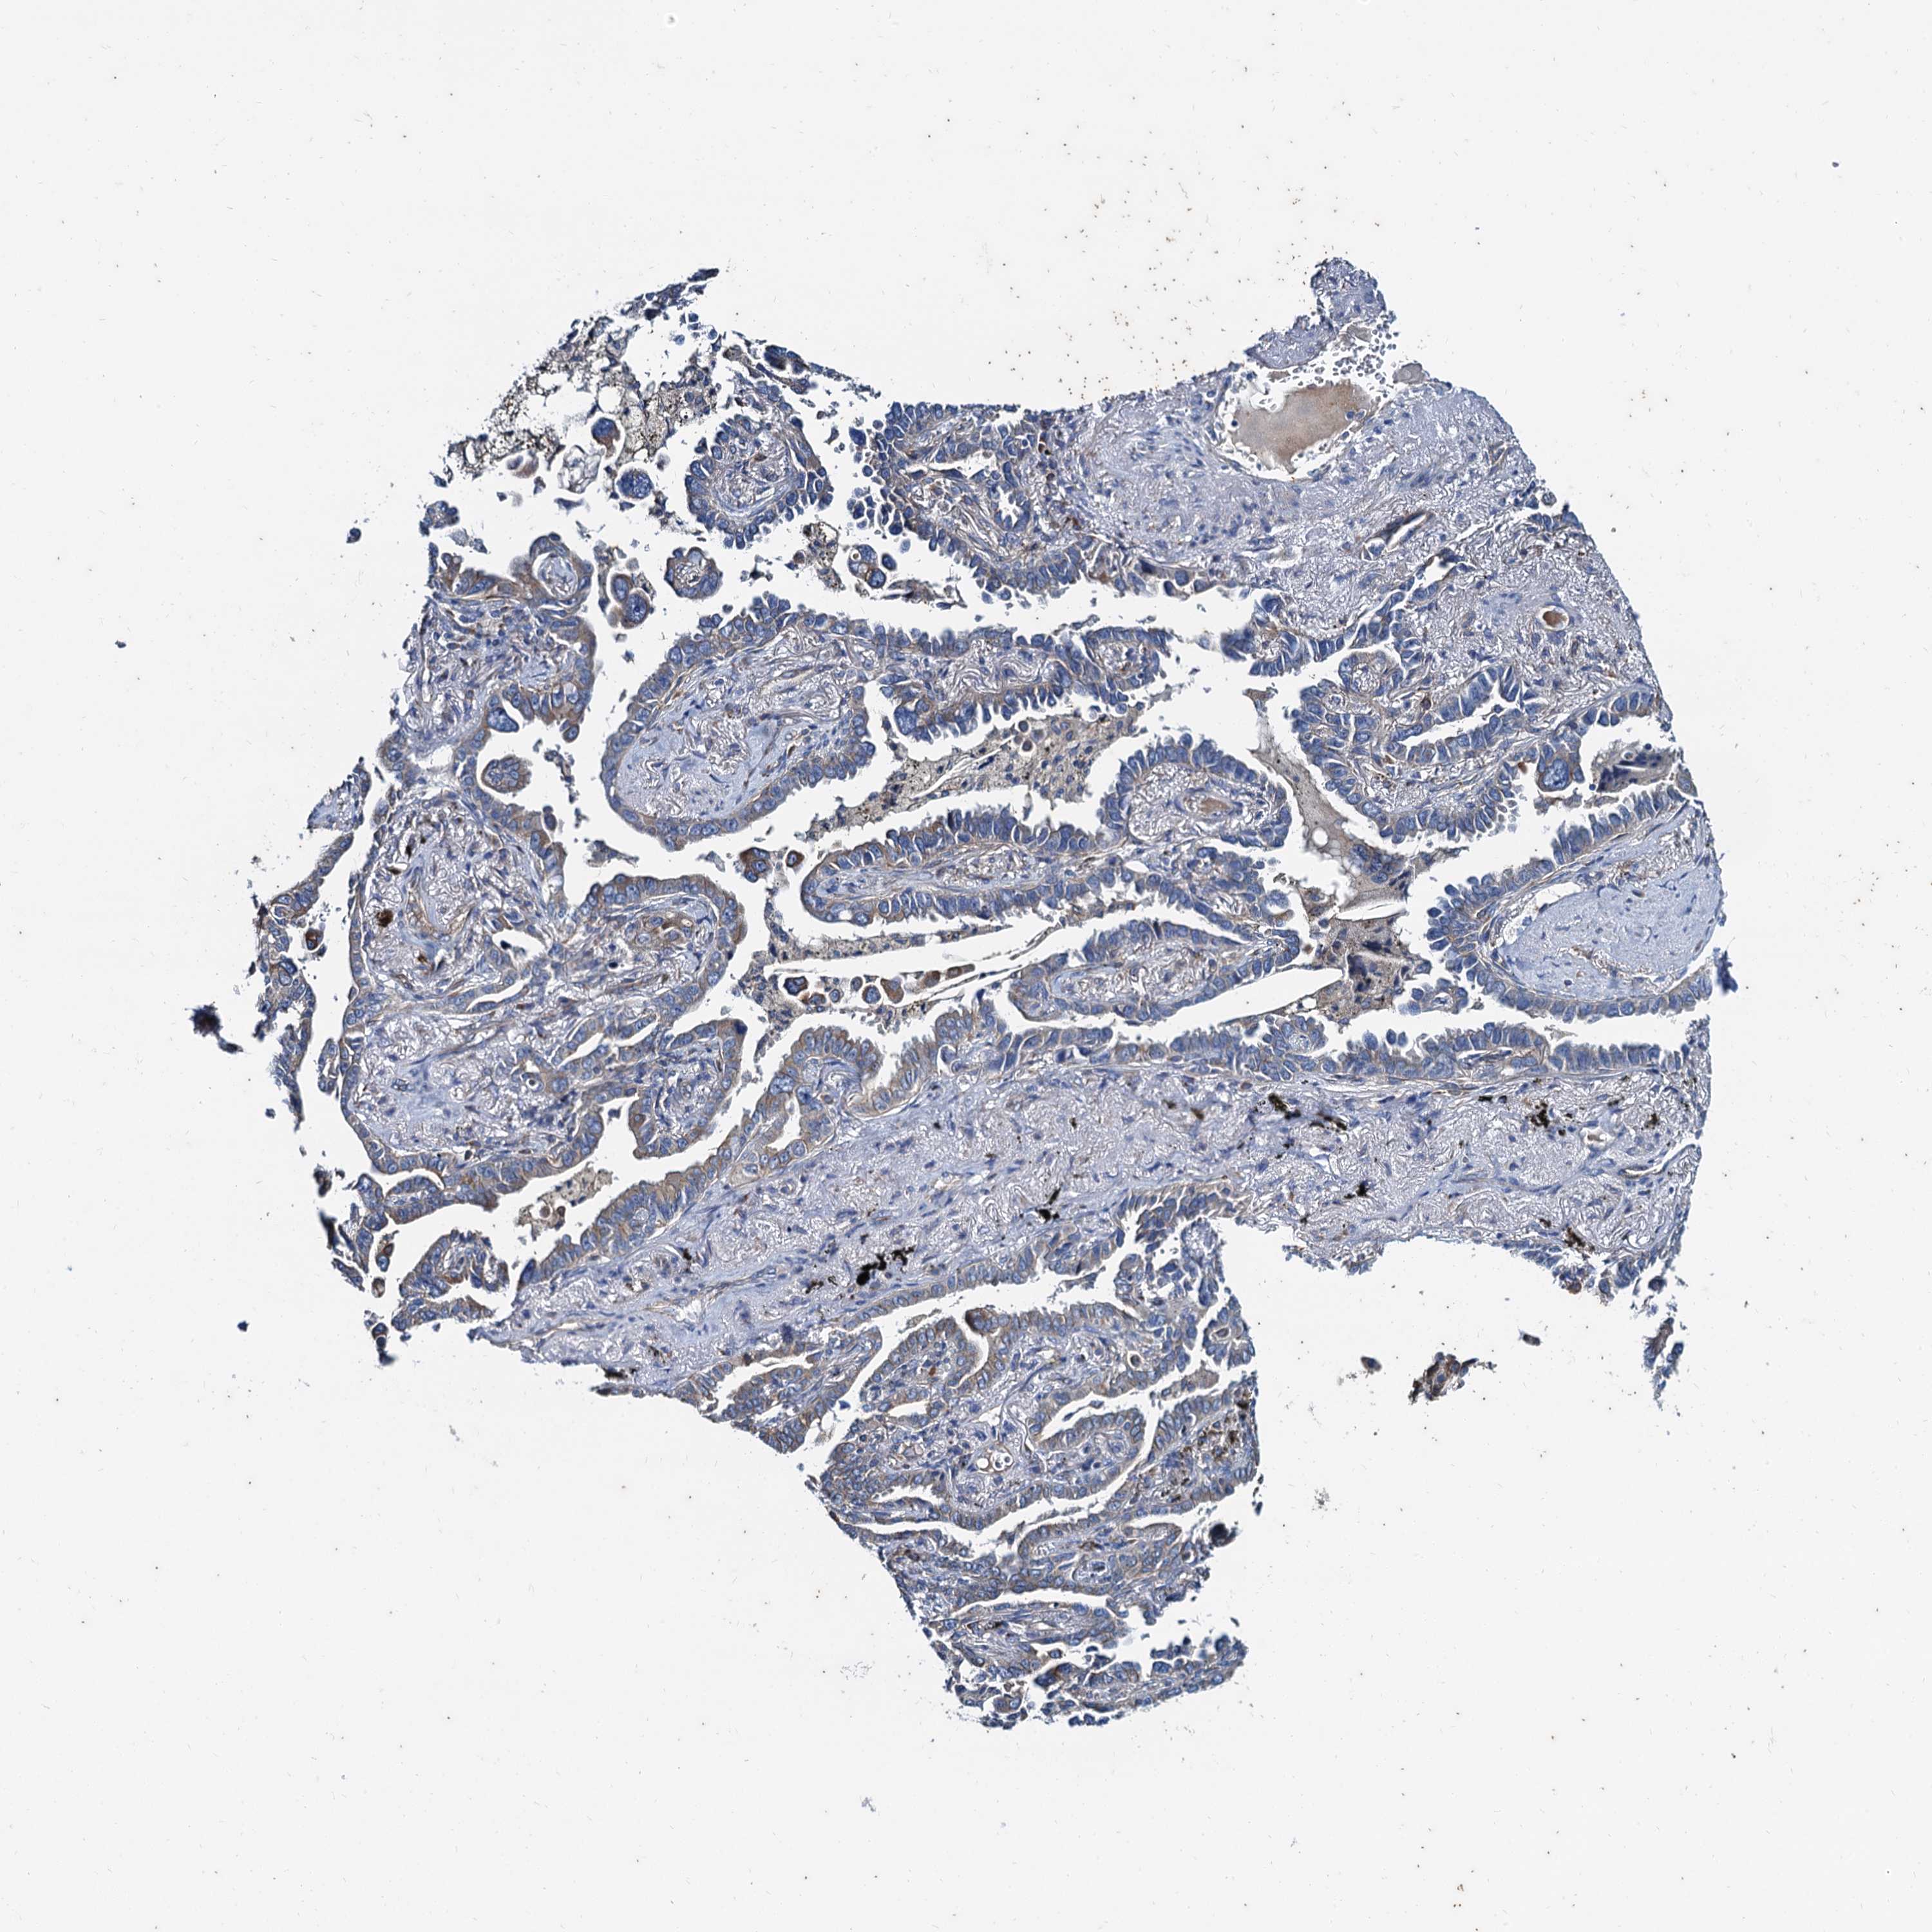

CANCER LUNG CANCER Show tissue menu

LUAD TCGA LUAD VALIDATION LUSC TCGA LUSC VALIDATION PROTEIN LUAD CPTAC PROTEIN LUSC CPTAC PROTEIN EXPRESSION